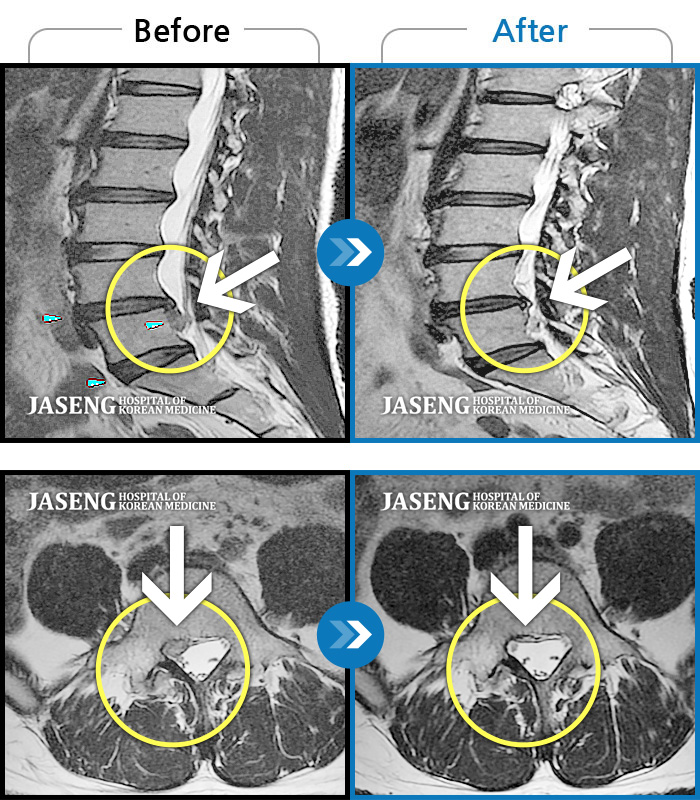

허리디스크

보라매 · 빈상은 원장

엉치에서 좌측 다리까지 통증, 저림으로 움직일 수가 없어요.

촬영시기

2024.08.03 ~ 2025.05.02

2025.12.12

조회수 68